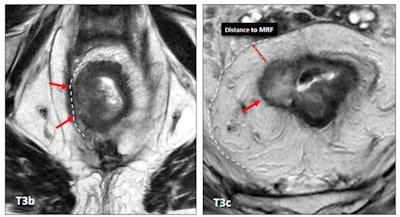

The treatment of a patient with rectal cancer mainly depends on the TNM (tumor, node, metastasis) stage and whether the mesorectal fascia (MRF) is involved. A T3b stage rectal tumor with MRF involvement (left, red arrows) compared to a T3c tumor with free MRF (right, red arrow). MRF involvement clearly worsens the prognosis of the tumor with a lower category of T staging. All images courtesy of Dr. María Canedo Antelo et al and presented at ECR 2023."MRF status is one of the most important risk factors for recurrence," they wrote. "A positive MRI-assessed margin between the tumor and MRF is defined as tumor lying within 1 mm of the MRF."

T3 category includes tumors with very different prognoses. Subdivision of T3 a/b and T3 c/d improves prognostic accuracy, they added.